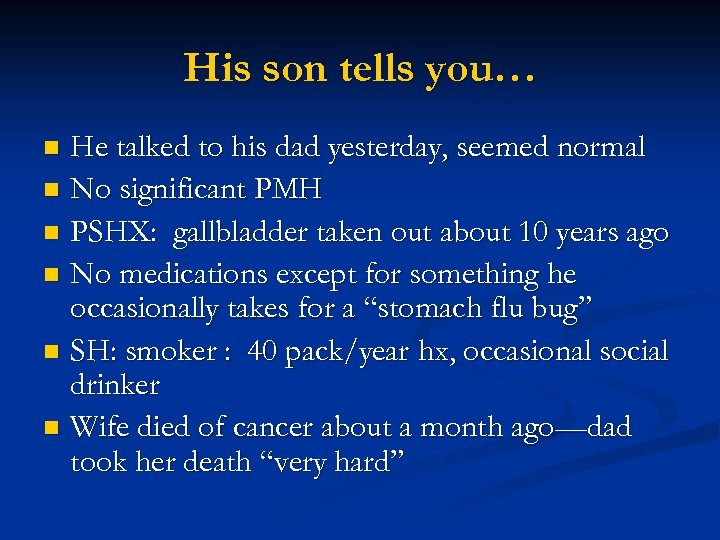

His son tells you… He talked to his dad yesterday, seemed normal n No significant PMH n PSHX: gallbladder taken out about 10 years ago n No medications except for something he occasionally takes for a “stomach flu bug” n SH: smoker : 40 pack/year hx, occasional social drinker n Wife died of cancer about a month ago—dad took her death “very hard” n

His son tells you… He talked to his dad yesterday, seemed normal n No significant PMH n PSHX: gallbladder taken out about 10 years ago n No medications except for something he occasionally takes for a “stomach flu bug” n SH: smoker : 40 pack/year hx, occasional social drinker n Wife died of cancer about a month ago—dad took her death “very hard” n